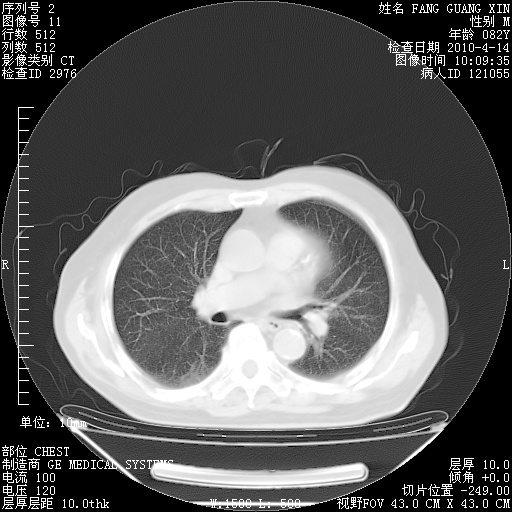

4月14日肺部CT

肺部CT平扫未见异常。